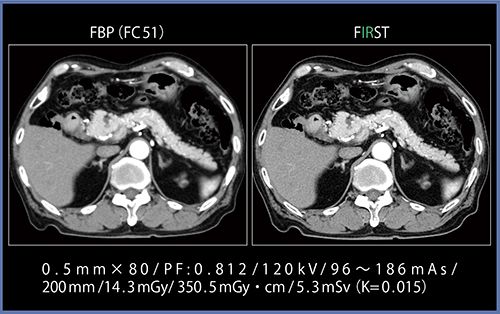

低コントラスト検出能の評価法はさまざまですが,FBPと比較した視覚評価では,FIRSTにてノイズやストリークアーチファクトを低減しつつ細かな粒状性を維持できていることがわかります。また,軟部組織の低コントラスト境界が明瞭化され,診断能の観点でメリットがもたらされます(図4)。

図4 FBPとFIRSTの低コントラスト検出能の比較

(画像ご提供:藤田保健衛生大学様)